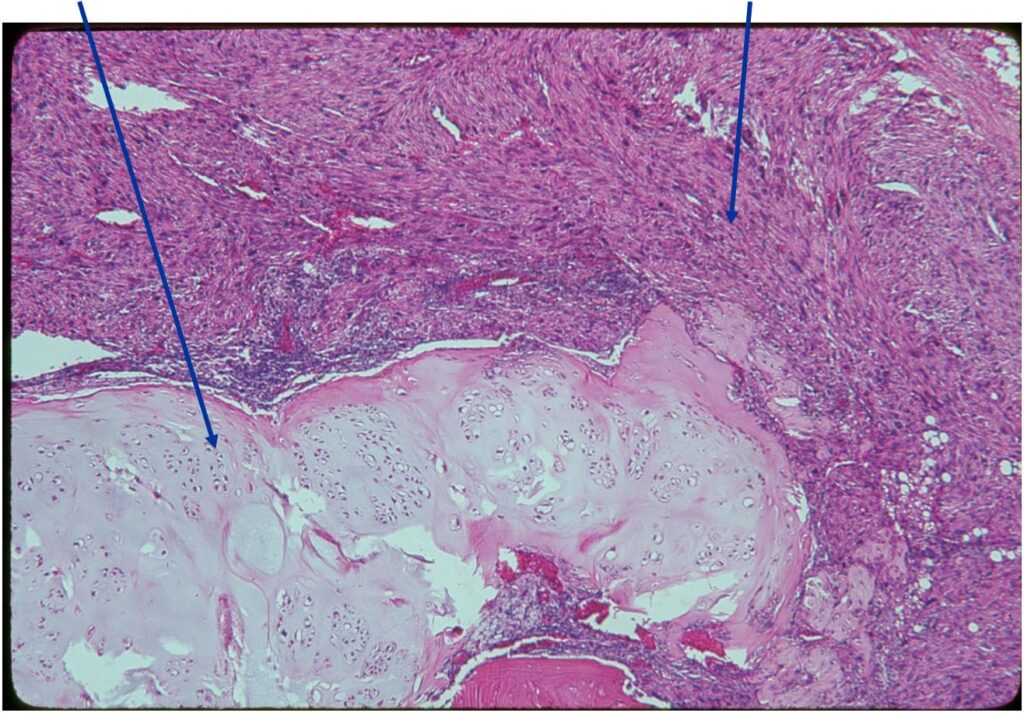

Junction of cartilaginous and noncartilaginous components is sharp and distinct. There are no dedifferentiated areas admixed in the middle of the cartilaginous areas

(Top Arrow) High Grade Dedifferentiated Spindle Cell Sarcoma Component

(Left Arrow) Low Grade Cartilage Component

(Right Arrow) Low Grade Cartilage Component

Dedifferentiated chondrosarcoma consists of a low grade malignant hyaline cartilage tumor associated with a high-grade nonchondroid spindle sarcoma. The two components are juxtaposed with abrupt clear demarcation line

- Chondrosarcoma component is often grade I (Low Grade Hyaline Type Cartilage)

- Dedifferentiated component